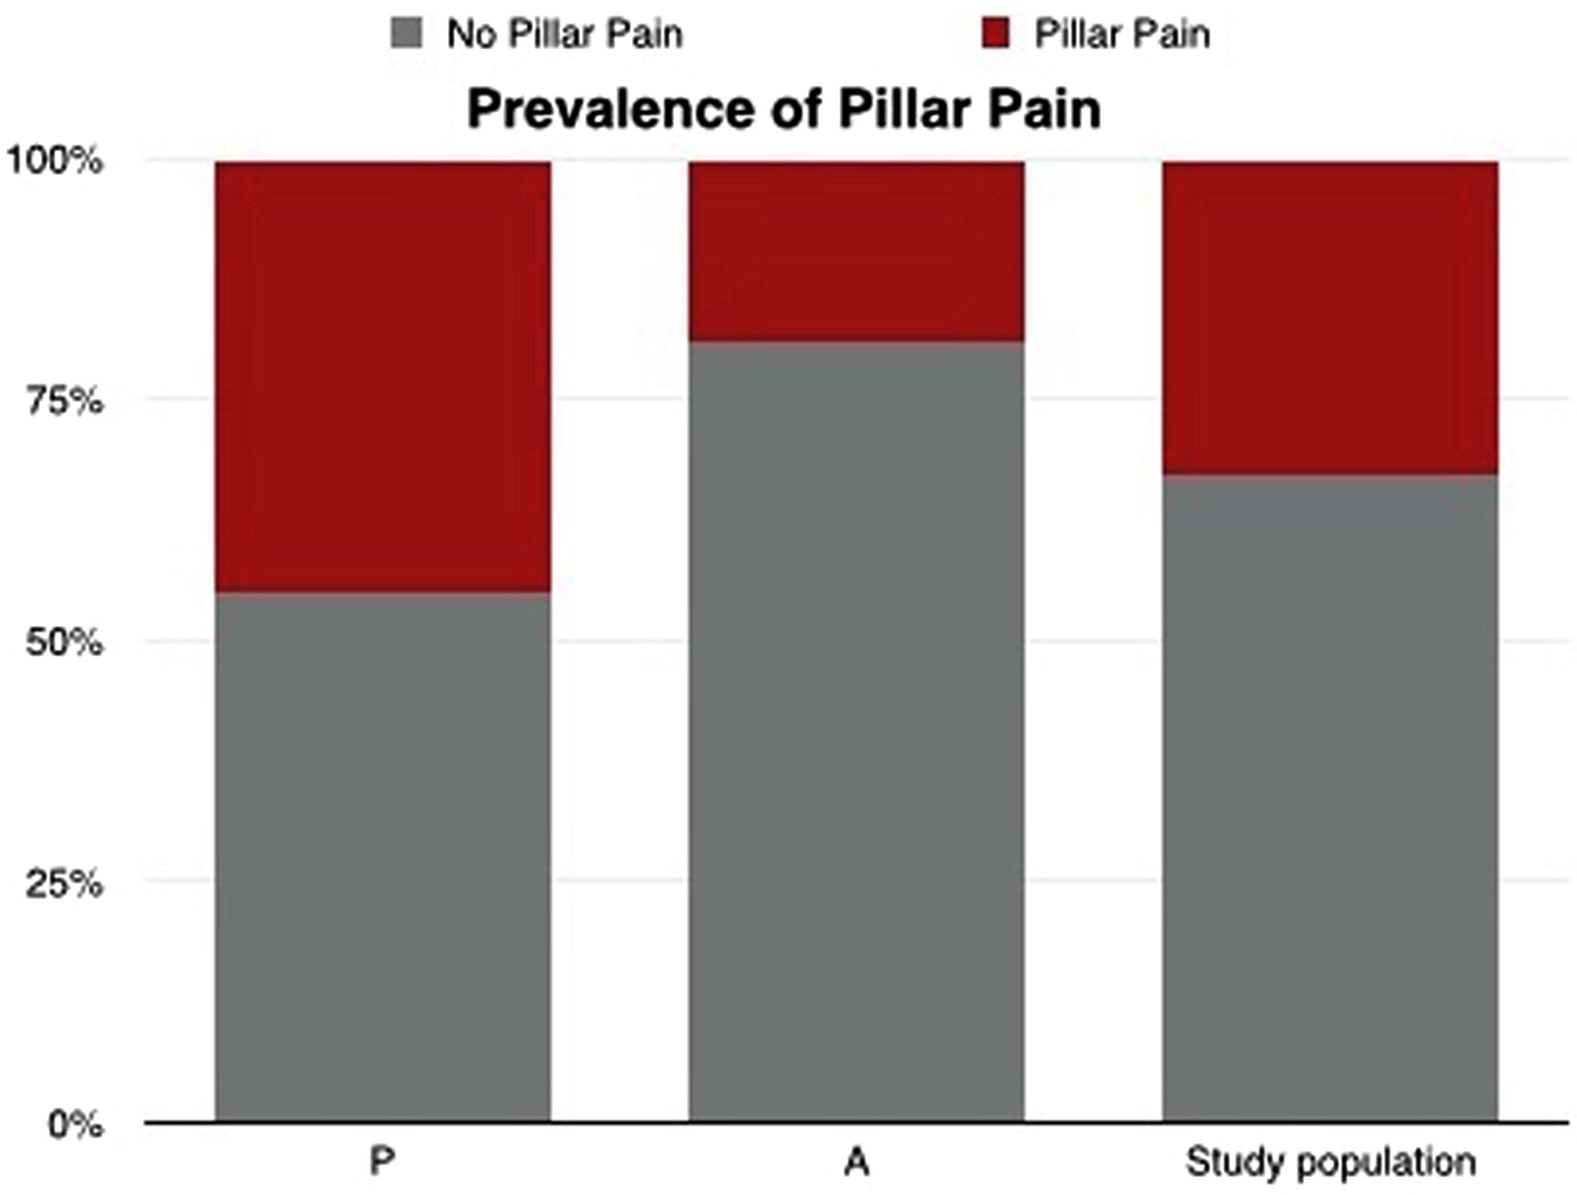

腕管松解术后 40 天服用 α-硫辛酸是否会降低发生支柱痛的可能性?

Filippo, B.、Granchi, D.、Roatti, G.、Merlini, L.、Sabatini, T. 和 Baldini, N. (2017)。腕管正中神经减压后α-硫辛酸:A ...

腕管手术后服用 α-硫辛酸 40 天可以降低发生支柱痛的可能性。

Filippo, B.、Granchi, D.、Roatti, G.、Merlini, L.、Sabatini, T. 和 Baldini, N. (2017)。腕管正中神经减压后α-硫辛酸:A ...